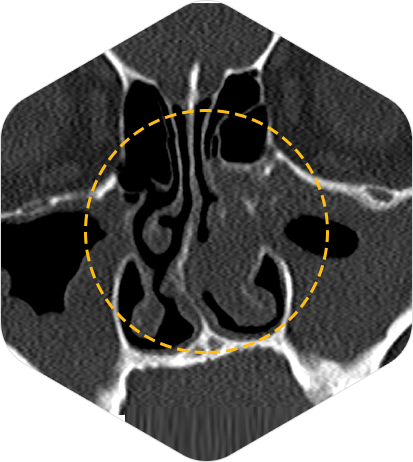

3D-CT, X-ray 촬영

3D-CT와 X-ray 촬영을 통해 내시경으로 환자의 대략적 골격구조 및 기도의 크기를 파악한 뒤 결과에 따라 입체 분석을 실시합니다.

비중곡만곡증 수술 전

비중곡만곡증 수술 후